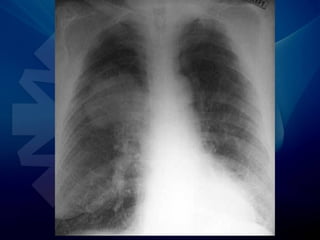

• Radiografía de tórax

• Rx de Tórax